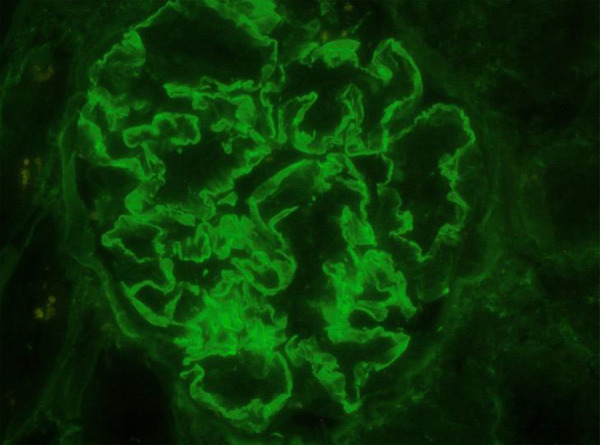

我们报告了一例女性非典型抗肾小球基底膜(anti-GBM)肾炎患者的病例,她同时患有肺分枝杆菌感染。肾活检显示新月体肾小球肾炎伴有50%的活动性新月体和线性IgG染色,但未检测到循环中的抗GBM抗体,患者也没有肺出血。尽管患者接受了抗生素、皮质类固醇激素和血浆置换术三联疗法治疗,但肾功能仍未恢复。一年后,她仍在进行维持性透析,但仍未摆脱阿维菌感染。

We present the case of a woman with atypical anti-glomerular basement membrane (anti-GBM) nephritis associated with concurrent pulmonary infection with Mycobacterium avium. A kidney biopsy showed crescentic glomerulonephritis with 50% active crescents and linear IgG staining, but no circulating anti-GBM antibodies were detected, and the patient did not have pulmonary hemorrhage. Despite treatment with a triple-regimen of antibiotics, corticosteroids, and plasmapheresis, the patient did not regain kidney function. One year later she is on maintenance dialysis and has still not cleared the infection with M. avium.